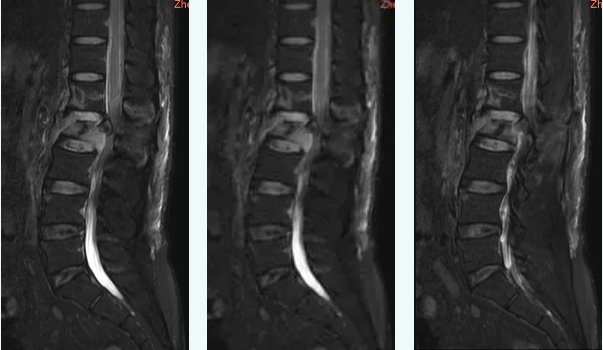

崔先生被送到医院时,他已经在床上不能动弹,神情中透露着深深的无助。得知情况后,医院骨科三病区专家团队立刻展开紧急的检查与讨论。在急诊入院的过程中,医生们首先为他进行了详细的辅助检查,包括影像学检查与神经功能评估。检查结果显示,崔先生的腰2椎体爆裂性骨折压迫了脊髓,导致了双下肢截瘫。

▲ 术前影像学检查